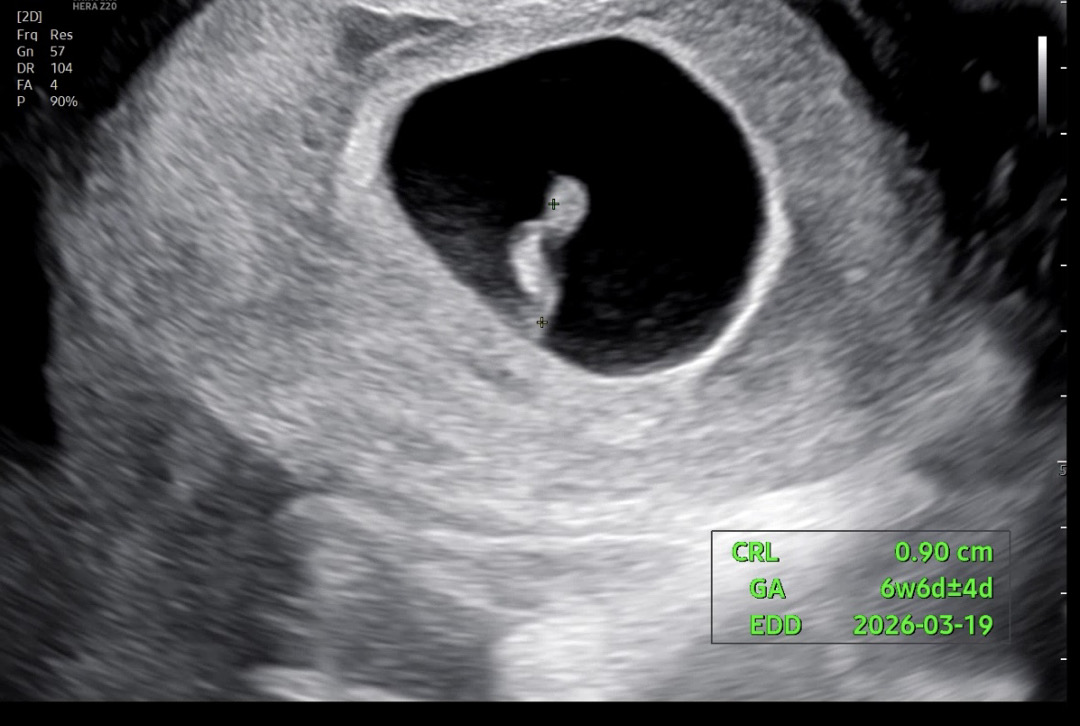

아기+심소 듣고왓어요6주6일인데

다들 6주 6일 예비맘님들 다들 아기 크기랑 심소 bpm어떠셧어요??

6주6일에 아기 0.93cm에 심소 158bpm이요!